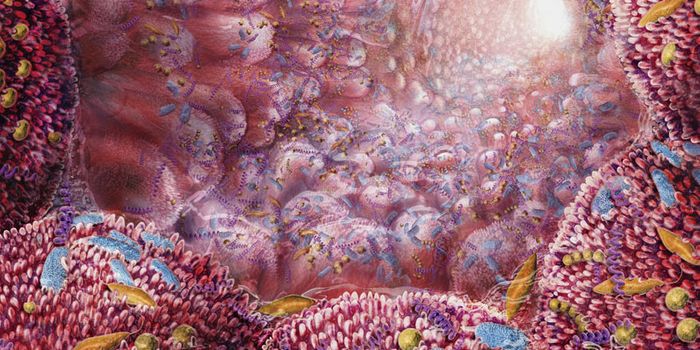

NOV 14, 2022ImmunologyThere are many types of microorganisms in the human gastrointestinal tract, and many of them perform important functions ...